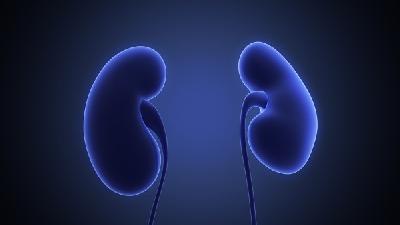

肾盂肾炎病人吃什么

想必大家对于有些疾病不是很陌生了吧,比如说肾病之类的肾盂肾炎,它给人们带来的是无尽的病痛折磨,甚至有时会消磨人的意志力,但在治疗过程中,吃的食物也会决定你之后的治疗效果,因此大家也需要在食物上加倍注意,那么,肾盂肾炎病人吃什么,下面我们就为大家说说吧。肾盂肾炎吃什么东西会比较的好?具体如下:第一、限制蛋白质肾盂肾炎发病3-6天时,由于肾小球率过滤的下降,会产...

肾盂肾炎能吃烤鸭吗

在现实生活中肾炎是一种常见的人体疾病,由于现代人们的生活水平的提高很多人不注意日常的饮食和作息时间,长期下去就会造成一些肾脏疾病,严重的患者还会引起一些身体并发症等,十分影响患者的正常工作和生活,也会给肾炎患者带来很多困扰,那么肾盂肾炎能吃烤鸭吗吗?下面就让我们一起来了解一下。鸭肉适合营养不良,水肿,或产后病后体虚之人食用;适合有内热内火之人,格外是有低热,...

肾盂肾炎的饮食注意事项

肾盂肾炎是由细菌感染所引起的,所以,要想自己远离该病的毒害,我们必须要做好预防感染的措施,以免深受其害,对于患有肾盂肾炎的患者来说,应该要注意日常饮食,那么肾盂肾炎的饮食注意事项有哪些,下面我们就为大家详细介绍一下。1、限制食盐患者的水肿和血容量,与钠盐的关系极大,每1克盐可带进110毫升左右的水,肾炎患者如进食过量的食盐,而排尿功能又受损,常会加重水肿症状...